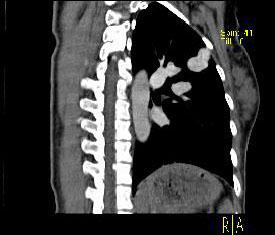

问题 男性,26岁,头晕、气逼三年余,CT检查如图所示,请选择的最可能诊断 ( )

选项 A、动静脉畸形 B、动脉瘤 C、毛细血管扩张症 D、毛细血管瘤 E、海绵状血管瘤

答案 A